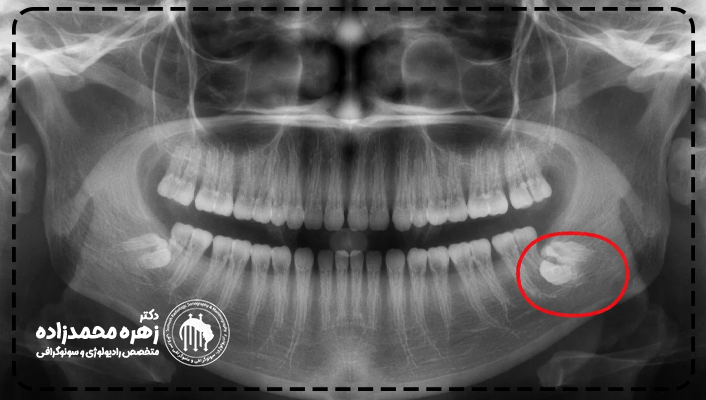

رادیوگرافی پانورکس یک نوع تصویربرداری اشعه ایکس است که نمایی سراسری از کل دندانها، استخوانهای فک و مفصلهای گیجگاهیـفکی را در یک تصویر نشان میدهد. این تصویر به شکل منحنی ثبت میشود و به همین دلیل تمام دندانها و فکها به صورت یکپارچه دیده میشوند.

رادیوگرافی پانورکس در تشخیص بسیاری از مشکلات دهان و دندان کاربرد دارد. این روش برای بررسی وضعیت کلی دندانها، ارزیابی دندانهای نهفته، بررسی رشد فک، مشاهده استخوان فک و حتی شناسایی برخی بیماریهای پنهان بسیار مفید است. به دلیل پوشش وسیع تصویر، دندانپزشک میتواند برنامهریزی دقیقتری برای درمان انجام دهد. از جمله مواردی که ستفاده میشود میتوان به موارد زیر اشاره نمود:

- تشخیص محل اصلی درد دندان

- درگیریها و مشکلات پری اپیکال

- ارزیابی دندانها برای تکنیک ارتودنسی

- برای پیگیری نیاز جراحی مرتبط با دندان عقل

- در تشخیص و یا ارزیابی سرطان در دهان و ناحیه فک

- برای تشخیص دادن دندان عقل که در لثهها نهفته شده است.

- بررسی و تشخیص بیماریهای پیشرفته و پرخطر دهان و دندان مانند کروبوبیسم

تصاویر بدست آمده از رادیوگرافی پانورکس، در واقع دندانها، استخوان فک و سایر استخوانها و بافتهای نرم کنار آنها را نشان میدهد. دندانپزشکانی که برای معاینه دندانهای عقل نهفته که دردی به همراه دارند، به تصاویری از دهان و دندان احتیاج داشته که تشخیص دهند آیا درد از همان ناحیه میباشد یا خیر؟ اگر نیست، پس مشکل میتواند از کدام ناحیه باشد؟ همه و همه اطلاعاتی است که تصاویر رادیوگرافی پانورکس در اختیار دندانپزشکان خواهد گذاشت. همچنین در تشخیص پوسیدگیهای دندان و یا ریشه و همچنین اطلاعات تصویری تحلیل رفتن استخوانها در فک نیز موثر است.

رادیوگرافی پانورکس چه بیماریهایی را نشان میدهد؟

رادیوگرافی پانورکس میتواند طیف وسیعی از مشکلات و بیماریها را آشکار کند. این تصویر به دندانپزشک اجازه میدهد ناهنجاریهایی را که با معاینه معمولی دیده نمیشوند، تشخیص دهد. برخی از مواردی که در پانورکس قابل مشاهده هستند عبارتند از:

- دندانهای نهفته و نیمهنهفته و موقعیت آنها

- کیستها و تودههای استخوانی

- تحلیل استخوان فک

- مشکلات مفصل فک

- عفونتهای گسترده دهان و فک

هر کدام از این موارد با بررسی دقیق تصویر قابل شناسایی و پیگیری هستند.